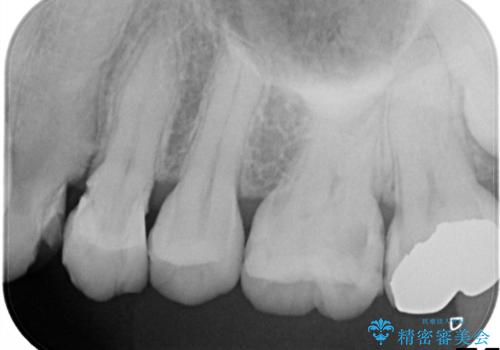

他院による虫歯治療(ドックスベストセメント)の再治療

- 他院でドックスベストセメントによる治療を受けたが、痛みがあり、歯がかけたことを主訴に来院されました。ドックスベストセメントは虫歯を取りきらずに抗菌性のあるセメントを充填し最終修復をする治療法ですが、充填物の中で虫歯が広がる可能性もあります。今回のケースでは特に虫歯を除去できていないため強度が低下し破折を認めました。

当院の治療は虫歯を除去した後、オールセラミッククラウンによる修復治療を行いました。